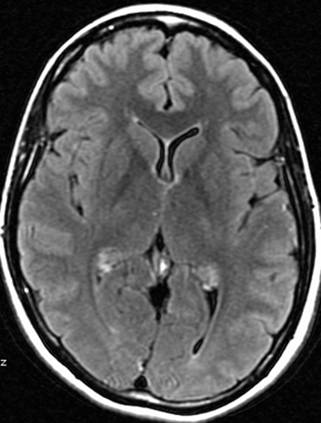

DWI就是平时头部磁共振影像看起来分辨率非常差,颗粒很粗的序列,现在在临床上主要用于急性脑缺血的早期诊断,早期,脑哽塞病灶,在这个序列上是高信号的--是由于细胞毒性水肿造成扩散降低造成的。

DWI就是平时头部磁共振影像看起来分辨率非常差,颗粒很粗的序列,现在在临床上主要用于急性脑缺血的早期诊断,早期,脑哽塞病灶,在这个序列上是高信号的--是由于细胞毒性水肿造成扩散降低造成的。

FLAIR 水抑制成像对脑部病理改变具有高度的敏感性,减轻水信号干扰,显示病理改变,鉴别病灶处是否为自由水,自由水为低信号。TR:9000ms TE:120ms TI:2500ms DWI:弥散加权成像,是目前能够检测活体组织内水分子扩散运动的无创性方法,是诊断脑梗塞最敏感的序列,超急性脑梗塞(小于6小时)细胞毒性水肿可明确诊断。TR:1500---2500ms TE:15---30ms

FLARI序列就是通俗所说的压水像,在这个序列中,脑灰质是高信号,也就是亮一些的,脑白质是低信号--这些类似于T2WI序列--但是在压水像上,脑脊液的信号是低的,也就是黑色的。这也是之所以称之为压水像的原因。 STIR脂肪抑制序列,在通常的T1WI和T2WI像上,脂肪都是高信号--亮的,在脂肪抑制序列--有许多种,频率抑制啊翻转恢复啊,正反相位啊--你不用明白这么许多,只要知道是压脂的序列,那么这个图像上的脂肪就是低信号--黑的。比如平时的腹部皮下脂肪,头皮下脂肪,就变成了黑色的。 一般的图像上,都会标出来FS--既是压脂序列。 DWI就是平时头部磁共振影像看起来分辨率非常差,颗粒很粗的序列,现在在临床上主要用于急性脑缺血的早期诊断,早期,脑哽塞病灶,在这个序列上是高信号的--是由于细胞毒性水肿造成扩散降低造成的。 DWI空间分辨率相对较低,靠近脑底处的磁敏感性伪影对额叶底部,颞极,小脑等处的病变评价带来影响,FLAIR不受影响。DWI上脑脊液为游离液体,其ADC类似于纯水,弥散快,在DWI上脑脊液信号明显衰减,也产生FLAIR中的黑液体效应,但二者的对比不完全相同,FLAIR除液体相为黑色外,其他组织保持T2对比。DWI的对比取决于另一组织特性参数ADC。DWI较FLAIR敏感,病变与正常组织对比更高,其异常信号范围大于常规T2和FLAIR序列。